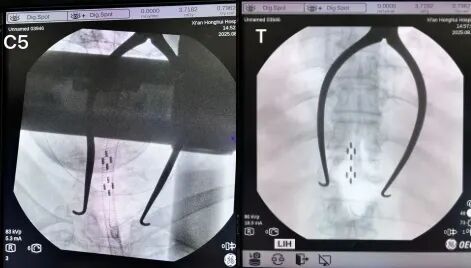

术中,张治国教授团队顺利置入双外科电极,术后在程控团队的精准调试下,短短一周肌张力就出现了明显改善。治疗前,她的左上肢肌张力达到改良Ashworth评级3级(肌肉痉挛较严重,被动活动困难);左下肢为2级(肌张力明显增加,被动活动有阻力)。术后一周后,经过参数调整,左上肢、左下肢肌张力均恢复正常。

术中影像